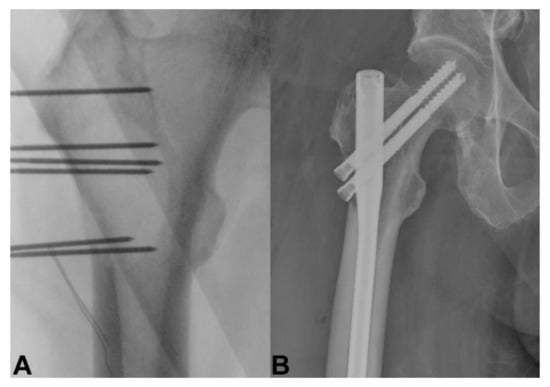

4. Bone Metastasis of the Extremities